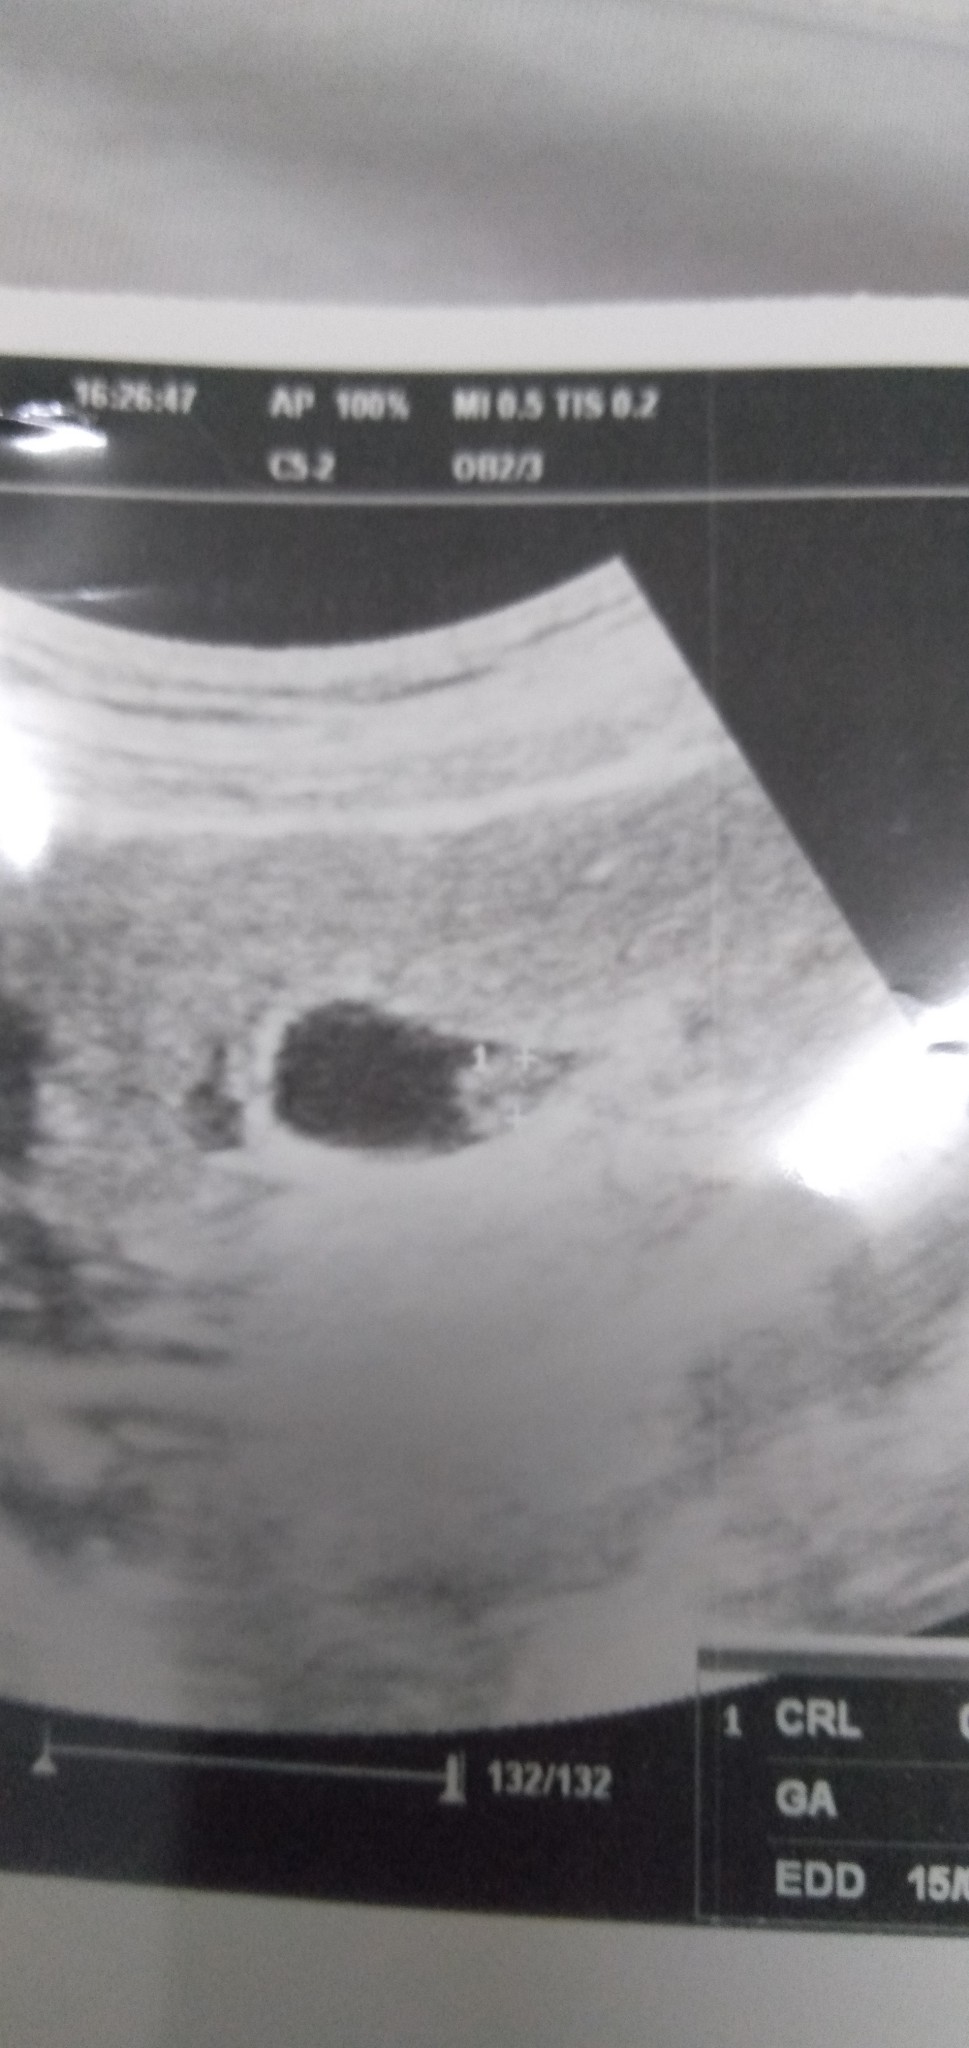

8weeks 4day

hye,so this morning i went to clinic for a scan. But doctor said she only see the sac. There is no baby. She suggested to wait for two weeks before i scan again. Is it normal? sorry for bad english

8 mnggu mmang tak nmpk lg baby tu..boasanya sac sj nmpk.at least 10 mnggu dan ke atas baru boleh nmpk baby

normal . 9,10 weeks ke atas baru nmpak , ikut org jugak laa . kena bnyak berdoa , fikir yg baik² .